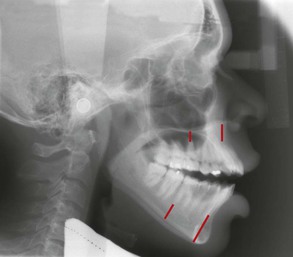

Studies10,11,13 have indicated that skeletal open bites are often related to excessive vertical growth of the dentoalveolar complex, especially in the region of the posterior maxillary molar (Fig. 9-3). Conversely, dental anterior open bites are primarily due to reduced incisor dentoalveolar vertical height14 (Fig. 9-4). The difference between these two types of open bites is also reflected in the occlusal planes. The skeletal type of malocclusion generally has occlusal contacts only at the molar level, with both occlusal planes diverging anteriorly,15 whereas the occlusal planes in the dentoalveolar open bite usually diverge from the first premolar forward (Fig. 9-5).

Figure 9-3 Excessive vertical height of the buccal segments is a common characteristic of skeletal anterior open-bite patients.

Figure 9-4 Reduced anterior dentoalveolar height characterizes a dental anterior open bite. A, Reduced incisal display as a result of restricted eruption of the maxillary incisors from a thumb-sucking habit. B, Anterior open bite from the finger habit. C, Reduced distance from the apex of the maxillary central incisors to the palatal plane.